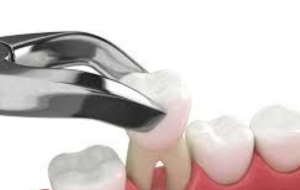

Exodoncia

Denominamos Exodoncia a la técnica de extracción de dientes o molares que por alguna razón se deben retirar de la cavidad oral. Realizamos exodoncias tanto de dientes, molares, raíces, premolares por necesidad ortodóntica, terceros molares (cordales), supernumerarios (dientes de más), caninos y demás dientes que se encuentren incluidos.